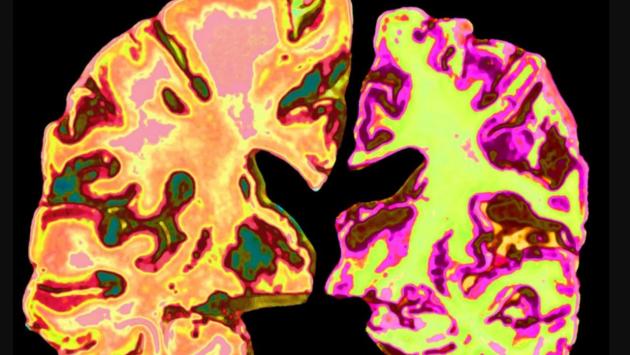

Вчені виявили простий спосіб зупинити розвиток Альцгеймера

Науковці з’ясували, що у людей із легкими когнітивними порушеннями та діагнозом Альцгеймера рівень літію в мозку значно знижений. Цей висновок підтвердили під час аналізу тканин мозку та крові.

Науковці виявили, що у людей з легкими когнітивними порушеннями та альцгеймером у мозку значно знижений рівень літію. Саме цей метал, у невеликих дозах, виявився ключовим для нормальної роботи нейронів.

Результати вразили: тварини, що раніше втратили здатність запам’ятовувати та орієнтуватися, знову почали успішно виконувати тести на пам’ять. Крім того, в їхньому мозку зменшилась кількість амілоїдних бляшок і патологічних тау-білків, які вважаються головними маркерами Альцгеймера.